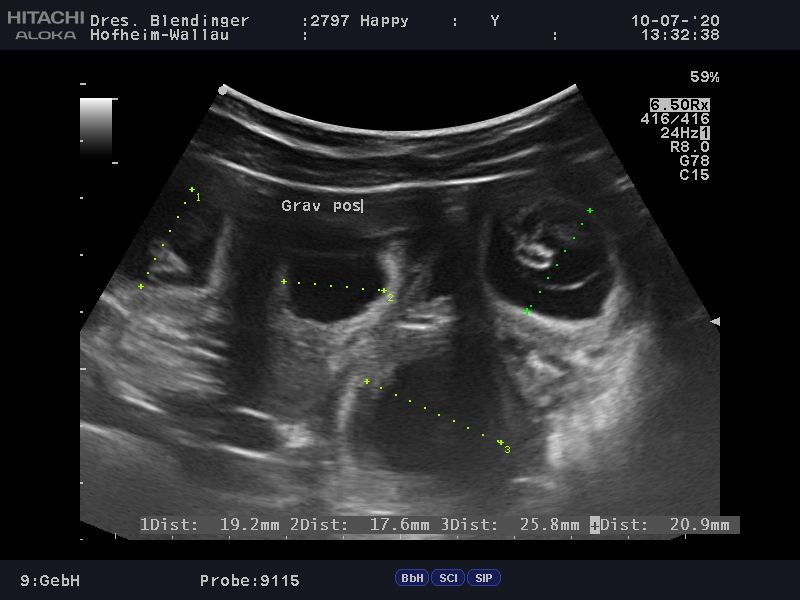

Wir haben tolle Neuigkeiten, Happy ist trächtig. Wir waren heute zum Ultraschall und laut Tierarzt, können wir uns über einen großen Wurf freuen.